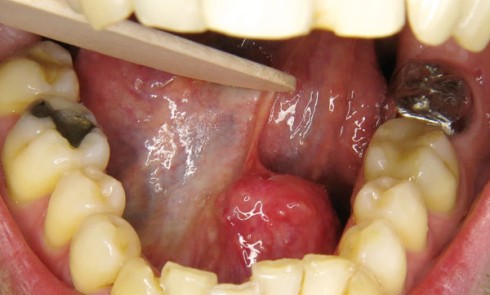

Article réservé à nos abonnés Une lésion du plancher buccal ?

1. Quels examens complémentaires prescririez-vous en première intention ?a. Radiographie panoramiqueb. Cliché de Blondeauc. IRMd. Echographiee. Cliché occlusal 2. Quel diagnostic...